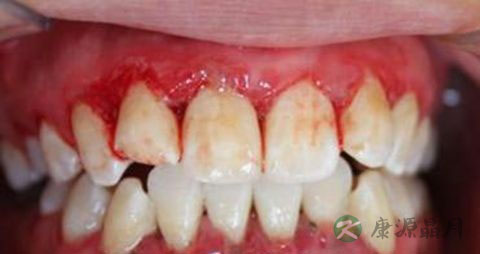

1、菌斑、牙石的局部刺激。菌斑、牙石的聚集,可由食物嵌塞、不良修复体、不良的口腔卫生习惯等引发,引起牙周组织炎症,如菌斑性牙龈炎、牙周炎等。

2、其他局部刺激因素(非菌斑牙石)及不良习惯。机械、化学、不良修复体、不良充填体、不良矫治器及张口呼吸等的刺激下,引发局部炎症,如增生性龈炎、牙周炎等。

5、内分泌的改变。在性激素升高、孕酮激素升高的影响下,使牙龈组织在轻微刺激下,引发非特异性炎症,导致牙龈出血、渗出增多、牙龈增生等。如青春期龈炎、妊娠期龈炎及牙龈瘤。

6、全身性疾病。如血液系统疾病、糖尿病、心血管疾病、肝肾功能异常、肿瘤等。致病方式通常是使全身的免疫力下降,进而导致对于局部刺激的抵抗力下降,诱发牙龈炎症;凝血系统障碍;血管的器质性变化、血流的动力学改变等等。